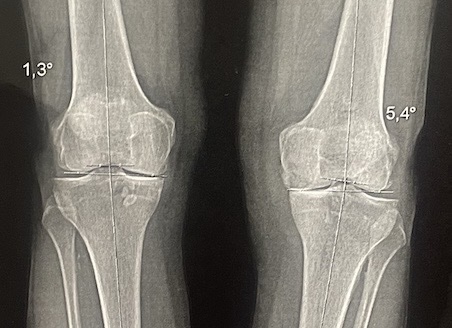

Et ce rôle est d'autant plus important qu'il se trouve du côté du genou, en charge lors de la marche et de la course : le ménisque interne pour les jambes arquées (en varus comme sur la radio) ou le ménisque externe pour les jambes en X (en valgus).